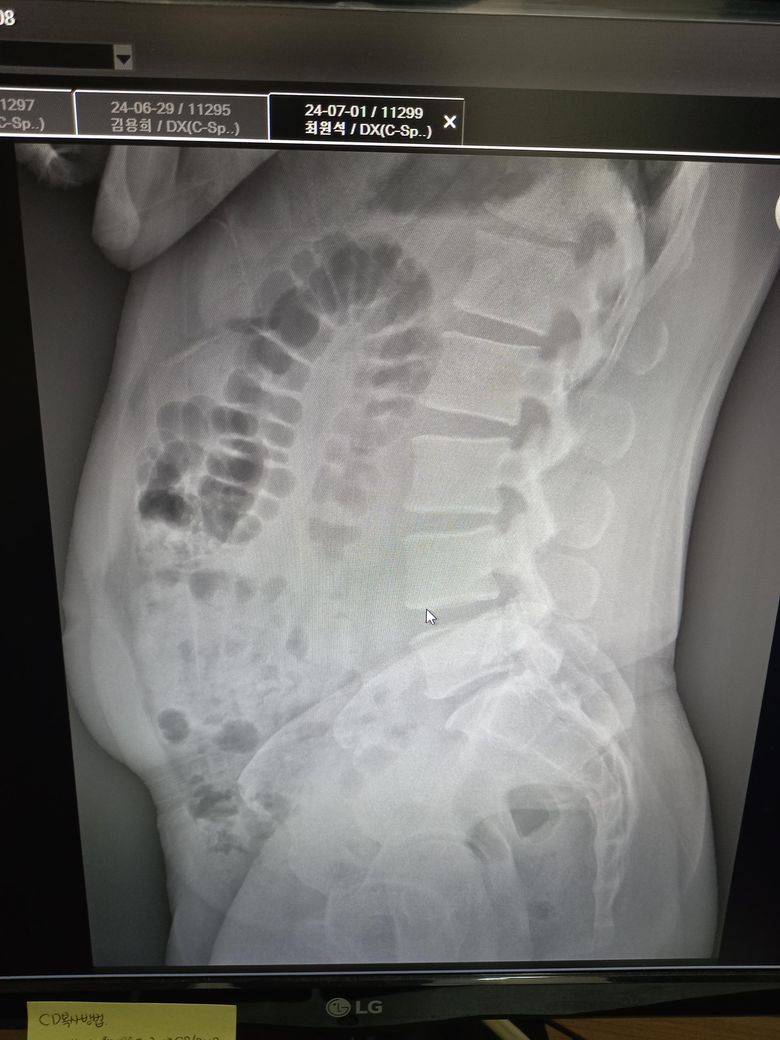

몸 상태 첨부합니다 풀어줘도 될까요?

또 지금이게 골반전방경사인거죠?

하복부와 허리 근육에 통증이 있을 때 마사지볼로 풀면 근육 완화될 수 있지만 통증이 지속되면 전문가의 상담을 받는 것이 좋습니다 골반전방경사로 보일 수 있지만 정확한 진단은 전문가가 옆에서 보면서 하는 것이 좋고 코어 강화 운동을 통해 골반과 허리의 균형을 잡는 것이 도움이 될 수 있습니다!

골반경사 맞으시고 우선 체중관리하시면서 도수치료 받고 체계적으로 교정치료를 받아보시는게 좋아보입니다

자세를 보아 골반은 전방경사로 생각되고, 내용처럼 브릿지, 데드버그 등 코어 운동 을 하면서 척추 중립을 유지하려는 훈련이 필요하겠습니다. 산소통 모양 근육이라고 하니까 정확하게 이해는 못하겠으나 척추 기립근이나 요방형근 등 폼롤러 등을 이용해 풀어주는것은 가능하겠습니다.

허리 근육 말씀하시는것 같은데 극돌기쪽을 조심해서 근육쪽 이완시켜주시는 것은 괜찮습니다. 그리고 배가 앞으로 나오면서 골반의 전방경사되어 있는 부분입니다. 복부의 탄력을 주시면서 자세 교정하시면 괜찮을 것 같습니다.